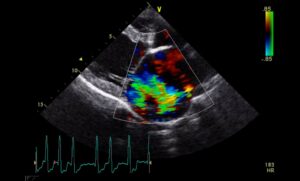

The effect of myxomatous mitral valve disease severity on packed cell volumeby Professor Adrian Boswood and colleagues at the RVC This work identified an inverse relationship between packed cell volume (PCV) and the severity of myxomatous mitral valve disease (MMVD) in dogs. The study was a retrospective analysis of prospectively collected data selected from a large population of dogs (n=289) on more than one occasion (n=1465 visits) between 2004-2017 at a research clinic conducted by the RVC in two primary-care practices in London. A control population of normal, unaffected patients seen at the same research clinic was included in the study. Appropriate statistical techniques were used to account for repeated measures from the same individual. Read more and access the publication